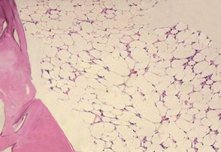

전형적인 골수소견은 조혈모세포(stem cell; 모든 종류의 혈액세포를 만들어낼 수 있는 능력을 가진 세포)의 감소와 함께 텅 빈 골수가 지방으로 차 있다.

- 조혈세포조직 감소

- 골수세포충실도의 감소

- 지방조직으로 대체

- 다른 질환과의 감별에 중요하고 확진을 위해 반드시 필요하다.